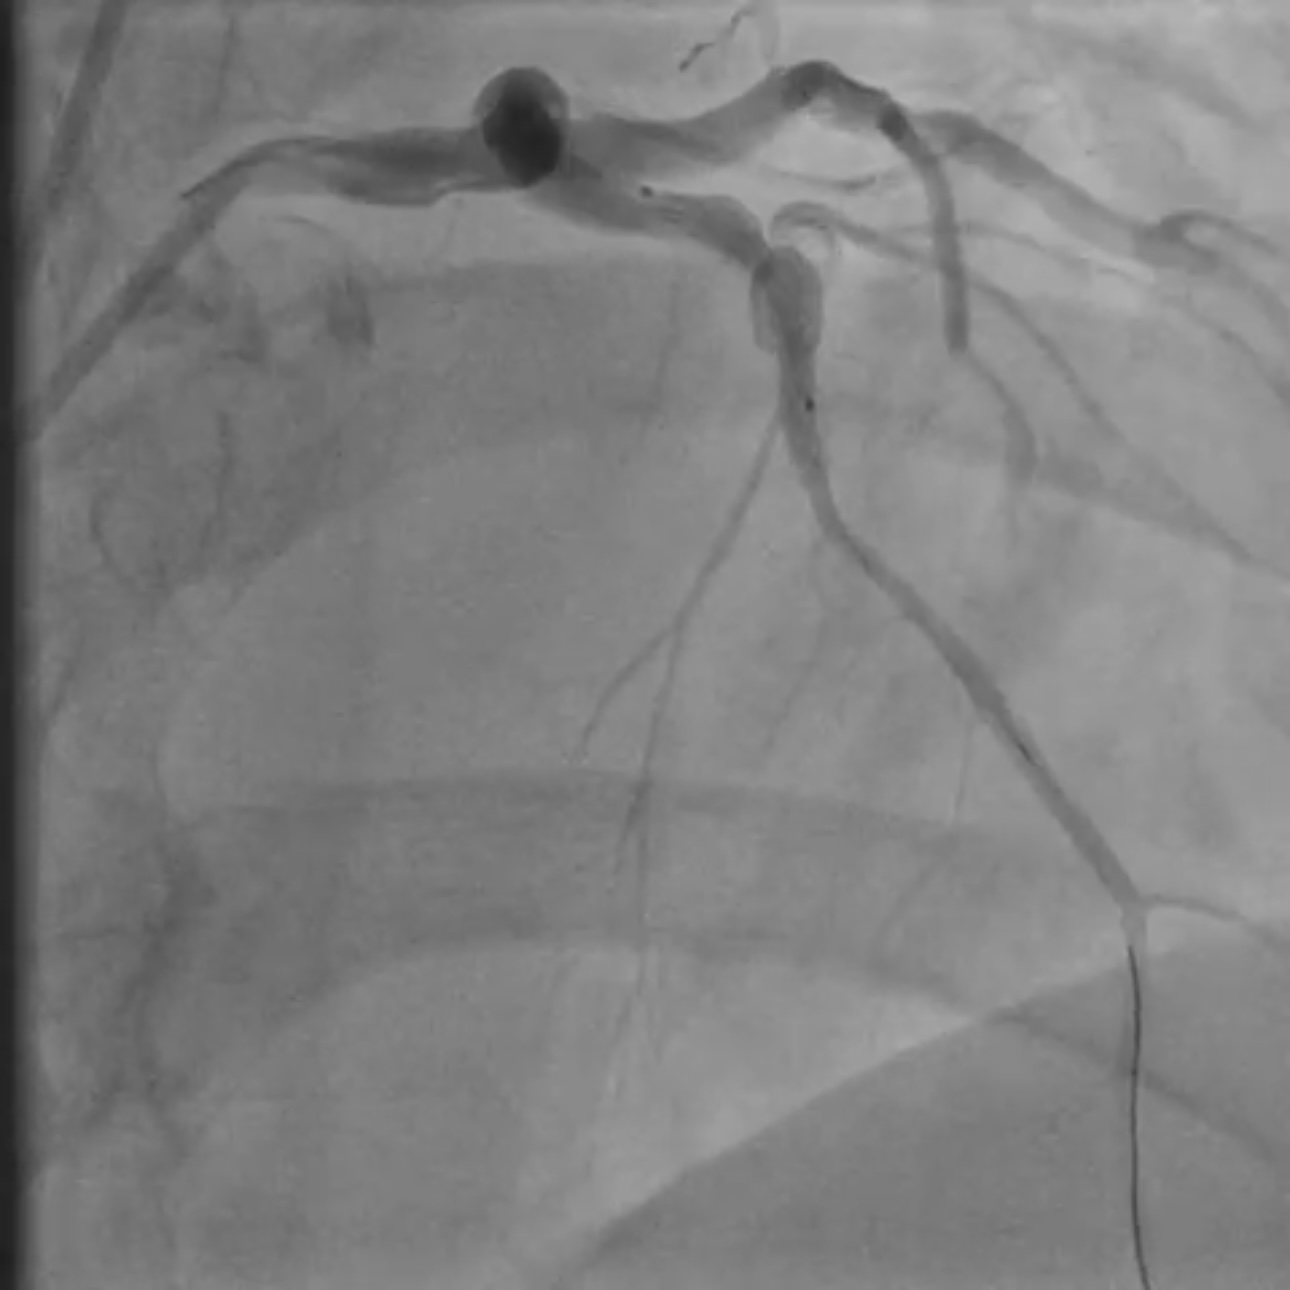

Coronary angiography revealed two severe stenoses in the mid left anterior descending (LAD) artery, separated by a short fusiform aneurysmal segment. The aneurysm was located between diseased segments and measured approximately 6 mm in diameter. A diagonal branch originated close to the proximal edge of the aneurysm. No thrombus or flow limitation was seen, and TIMI 3 flow was maintained pre-intervention.

Coronary angiography revealed two critical stenoses in the mid–left anterior descending (LAD) artery separated by a short fusiform aneurysmal segment. A diagonal branch originated near the proximal aneurysm margin. Implanting a covered stent was avoided due to the high risk of diagonal branch occlusion, and a drug-eluting balloon (DEB) strategy was rejected because it offered no vessel scaffolding and could destabilize the aneurysmal wall. A dual drug-eluting stent (DES) bridging technique was selected to stabilize the aneurysmal segment while maintaining branch perfusion. The procedure was performed via right radial access using a 6F XB guide catheter for enhanced support. A floppy guidewire was advanced into the distal LAD. Lesion preparation was performed with a 2.5 mm semi-compliant balloon. A 3.0 ¡¿ 15 mm DES was first deployed distally to treat the distal stenosis and establish a stable anchoring platform on healthy vessel. A second DES (3.5 ¡¿ 22 mm) was then implanted across the aneurysmal segment, with distal overlap onto the first stent to secure the construct outside the aneurysm. The proximal landing zone was carefully positioned in healthy vessel proximal to the aneurysm. Post-dilatation was deliberately limited to the landing zones with a non-compliant balloon to minimize mechanical stress on the aneurysmal wall. Final angiography showed optimal stent expansion, preserved flow to the diagonal branch, no dissection or perforation, and TIMI 3 flow. The patient received unfractionated heparin during PCI and dual antiplatelet therapy (aspirin + ticagrelor) per ACS guidelines.